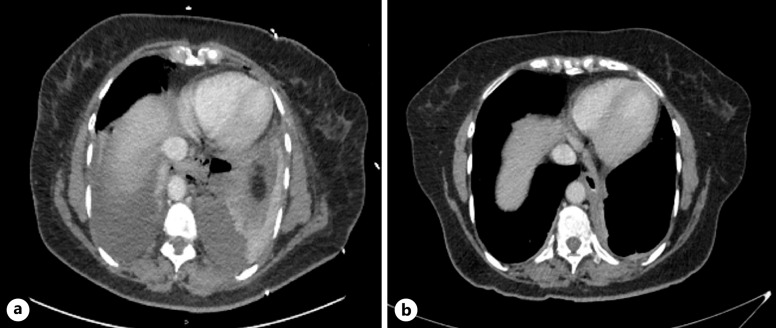

简介布尔哈韦综合征是一种罕见的疾病,发病率和死亡率都很高。及时干预可大大改善预后,手术是传统的主要治疗方法。最近,治疗性内窥镜技术的进步使人们对腔内真空疗法(EVT)越来越感兴趣,这是一种微创技术,可以对伤口进行清创和引流,促进肉芽组织的形成。EVT 具有积极的临床效果,包括与手术和支架治疗吻合口漏相比死亡率较低,其次是食道穿孔。EVT在欧洲已被广泛采用,但在英国却鲜有报道:我们报告了三例 Boerhaave 综合征病例,这些病例均使用 Eso-SPONGE ®(B.Braun Medical Ltd,英国谢菲尔德)EVT 成功治愈。EVT包括将聚氨酯海绵放入伤口腔内。首先对创腔进行评估,然后通过导管插入海绵,最后拔出导管。确认海绵位置,必要时进行调整。海绵通过经鼻引流管连接到持续负压吸引器,每 3-5 天更换一次。由于被认为不适合手术,所有 3 名患者都被转诊接受了 EVT。所有患者均恢复良好,并已出院回家:结论:对于不适合手术的波尔哈韦综合征患者,EVT 是一种有效的治疗策略。使用 Eso-SPONGE 有助于引流化脓灶和闭合缺损,使患者完全康复。我们的研究结果支持现有的证据,即 EVT 是治疗 Boerhaave 综合征的一种很有前景的方法。

Case presentations: We report three cases of Boerhaave syndrome, successfully managed with EVT, using the Eso-SPONGE ® (B.Braun Medical Ltd, Sheffield, UK). EVT involves the placement of a polyurethane sponge into the wound cavity. The cavity is initially assessed, then an overtube is introduced through which the sponge is inserted, and then the overtube is removed. Sponge position is confirmed and adjusted if necessary. The sponge is connected via a trans-nasal drain to continuous negative pressure suction and is changed every 3-5 days. Having been deemed surgically unfit, all 3 patients were referred for EVT. All patients made excellent recovery and were discharged home.